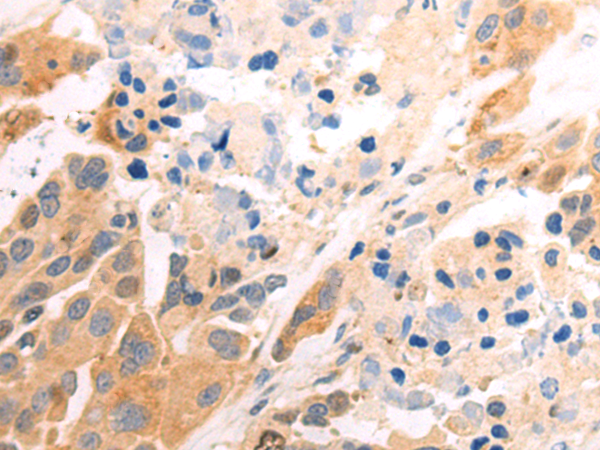

分类: 科研抗体货号: P09458别名: MIC2; HBA71; MIC2X; MIC2Y; MSK5X应用: WB,IHC反应种属: Human